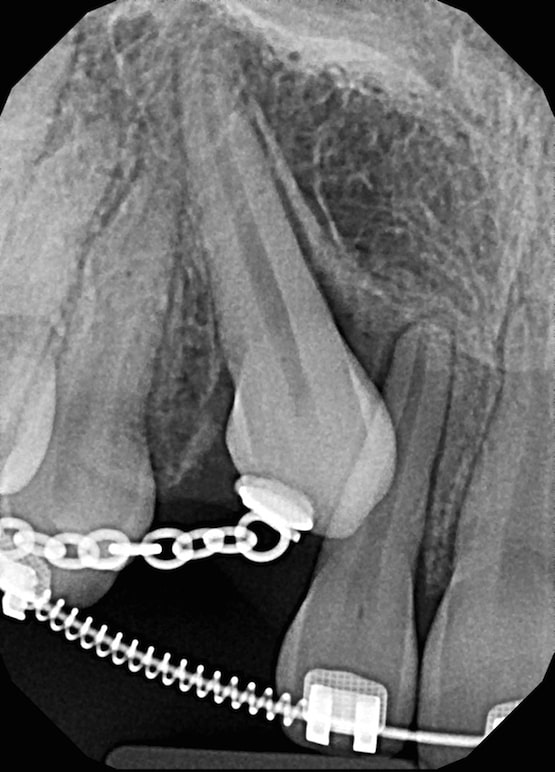

When the canine will not erupt spontaneously, the orthodontist and oral surgeon will work together to help it erupt. Each case must be evaluated on an individual basis, but treatment will usually involve a combined effort between the orthodontist and the oral surgeon. The oral surgeon will expose and bracket the impacted canine.

The goal is to erupt the impacted tooth and not to extract it. Once the tooth has moved into its final position, the gum around it will be evaluated. In some circumstances, there may be some minor “gum surgery” required.